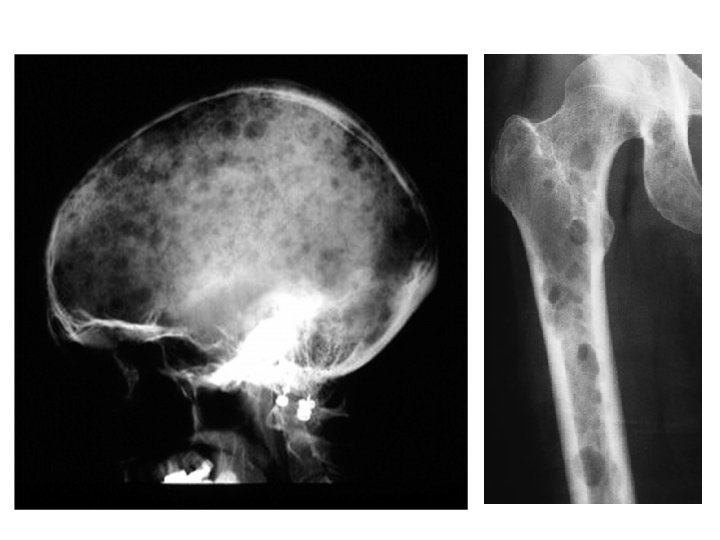

Multiple Myeloma / Plasmacytoma - A malignant B-cell lymphoproliferative disorder of the bone marrow with plasma cell predominating. - Results in bone marrow cell proliferation and increased osteoclastic activity which lead to osteoporosis and lytic lesions throughout the skeleton (myelomatosis). - Plasmacytoma : is a large colony of plasma cells aggregates in one bone. Typical patient �� 45 -65 year old with weakness, bone pain backache with or without pathological Fracture. - Also, signs of hypercalcemia (thirst, polyuria and abdominal pain) plasma proteins abnormalities, increased blood viscosity and anemia -Late secondary features are due to renal dysfunction and spinal cord or root compression caused by vertebral collapse.

- X-ray : ü Multiple “punched out” defects in the skull, pelvis and proximal femur …’geographic map’ ü Crushed vertebra ü Osteocytes lesion in a large bone metaphysis Multiple myeloma is one of the commonest causes of osteoporosis and vertebral compression Fracture in men >45 y.